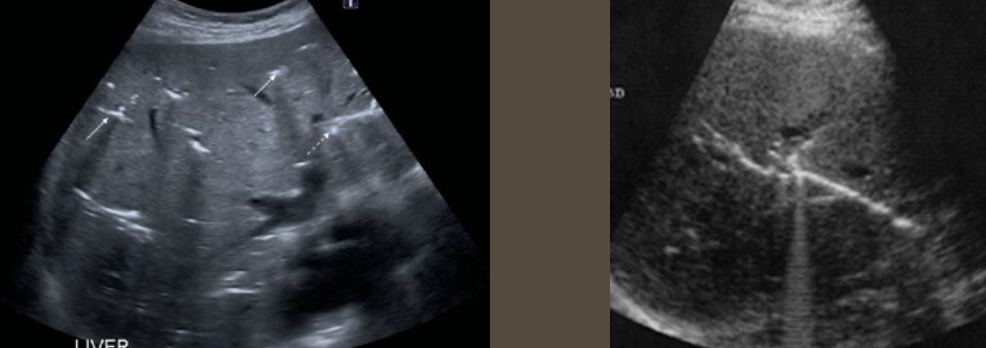

FNH (Focal Nodular Hyperplasia) → common, benign liver mass

2D US: well-defined, ~5 cm, usually solitary, central hypoechoic scar, isoechoic to hypoechoic to liver

color doppler: central scar → stellate scar doppler pattern (pinwheel)

DDX: hepatic adenoma, hemangioma, HCC